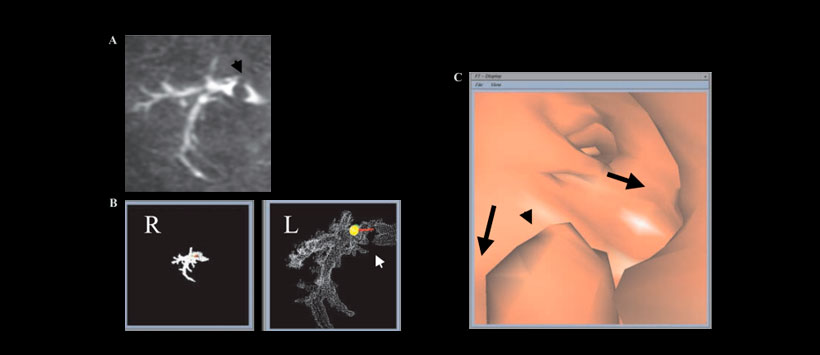

Figura 3: a) imagen de sialoradiografía mediante RM (Sialoendoscopia virtual 3D) de un hombre de 18 años con cálculos en los conductos izquierdos de Wharton. (b) imágenes en 3D que muestran la presencia de un cálculo salival en los conductos principales (flecha) y la expansión del conducto principal cerca del orificio de la glándula submandibular izquierda. (c) Vista endoscópica de RM virtual que muestra el cálculo cerca del orificio del conducto de la glándula submandibular izquierda (punta de flecha), la expansión y la bifurcación de los conductos principales (flechas).